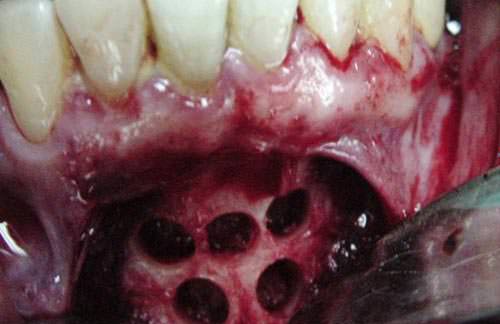

Después de 6 meses de la intervención, se procedió al retiro de la membrana evidenciándose la presencia de tejido óseo mineralizado, con aumento del piso del seno maxilar y regeneración ósea en sentido horizontal y vertical de la cresta ósea alveolar (Fig. 15 y 16).

Fig.15

Fig.16